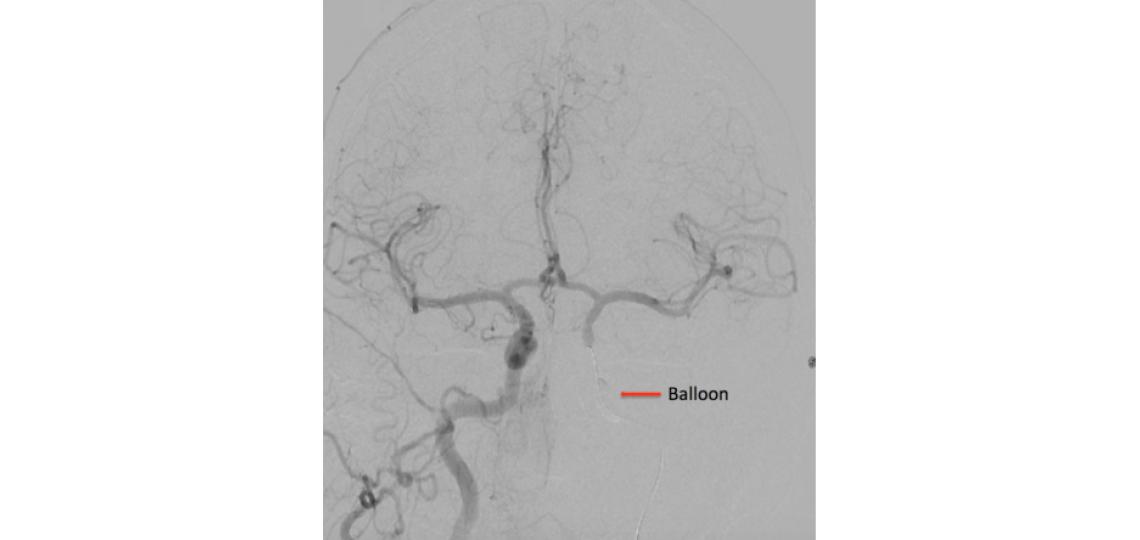

AP (A) and lateral (B) view of a right common carotid injection (normal angiogram)

A right internal carotid artery injection with a balloon inflated in the left internal carotid artery (arrow) shows good collateral filling to the left hemisphere during a test occlusion of the left internal carotid artery.